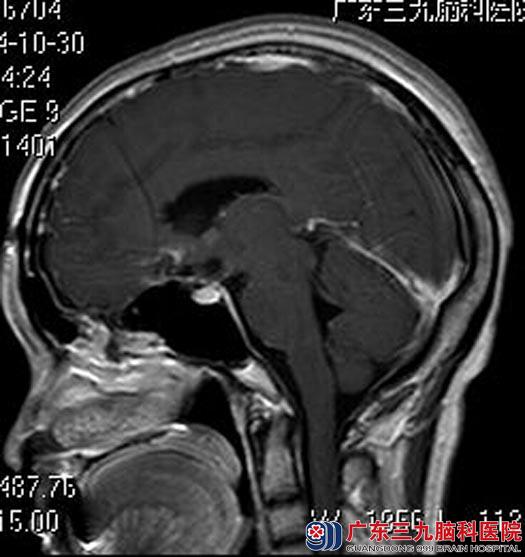

他们来到广东三九脑科医院,头颅MR检查提示鞍上池内占位病灶,大小约34.9mm×30.6mm×27mm,考虑颅咽管瘤可能性大。

手术前